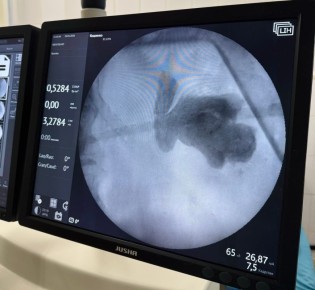

Совершили чудо и подарили надежду на здоровое будущее. Урологи 7-й Ивановской городской больницы удалили пациентке камень, который занимал почти всю площадь почки. Это максимальный размер образования, возможный для организма....